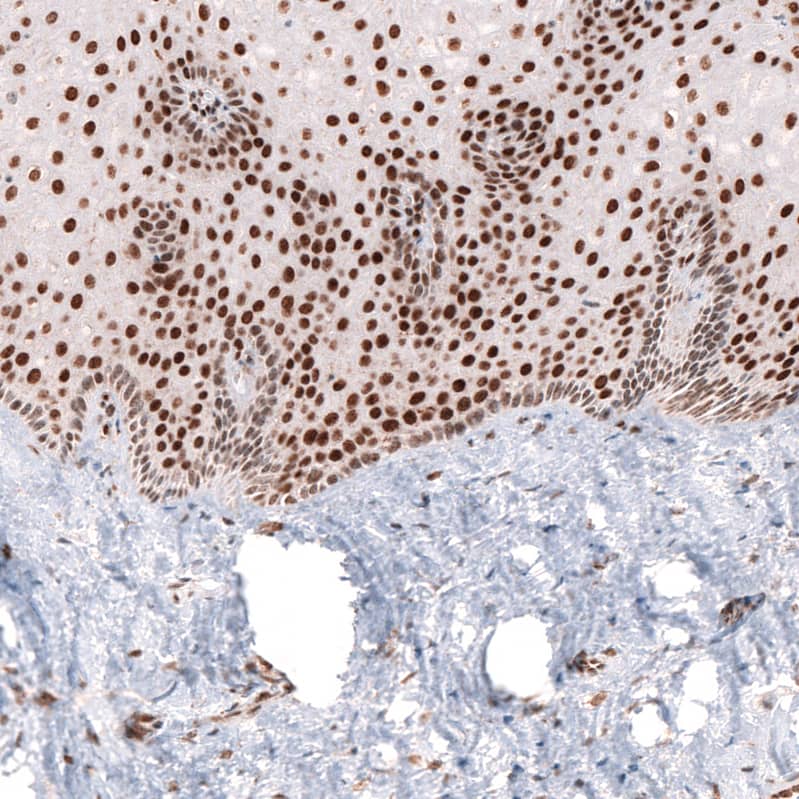

Staining of human uterine cervix shows strong nuclear positivity in epithelial cells.